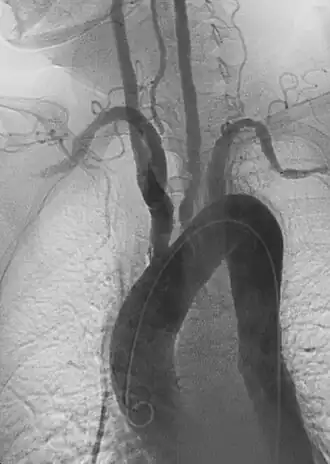

Angiografia anterior de aorta e grandes vasos com estenose.

A arterite de Takayasu é uma vasculite crônica desencadeada por uma reação autoimune em pessoas com predisposição genética. [2] Acomete principalmente a aorta e seus ramos principais, as artérias maiores do corpo, levando ao espessamento inflamatório e ao dano da parede dos vasos, com subsequente estenose ou formação de aneurisma[3]. Raramente afeta outras artérias, como as coronárias, renais, mesentéricas ou femorais.

Durante o exame físico uma diferença entre os pulsos radiais esquerda e direita podem ser percebidos, geralmente um dos pulsos está ausente e o outro aumentado. A estenose dos ramos da aorta afetados pode ser auscultada. Estudos de imagem (como ressonância magnética, raios-X e angiogramas), que mostram a localização e a gravidade da inflamação e aneurismas nas artérias.[6]